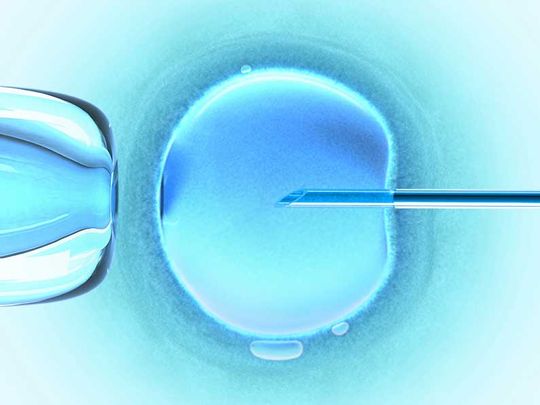

Desde hace 15 años, ejerce como especialista en

gineco-obstetricia, colposcopia e infertilidad, apoyando a las familias a cumplir su anhelo de lograr un embarazo.

La Dra. Margarita Rosa Viana Pizarro te atenderá desde una consulta ginecológica hasta desarrollar los mejores y más vanguardistas tratamientos para ayudar a lograr la fecundación.